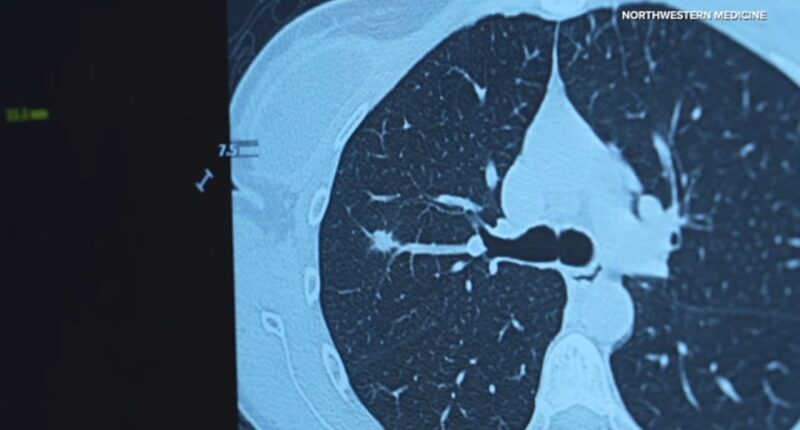

It’s why Northwestern Medicine is helping to expand low dose CT screening by launching a comprehensive lung health center to detect lung, heart and bone conditions earlier.

Northwestern Medicine said their early lung screening scan takes less than 10 seconds and doesn’t need any dyes but does provide a complete picture of the chest cavity, creating a baseline image patients can keep for life.